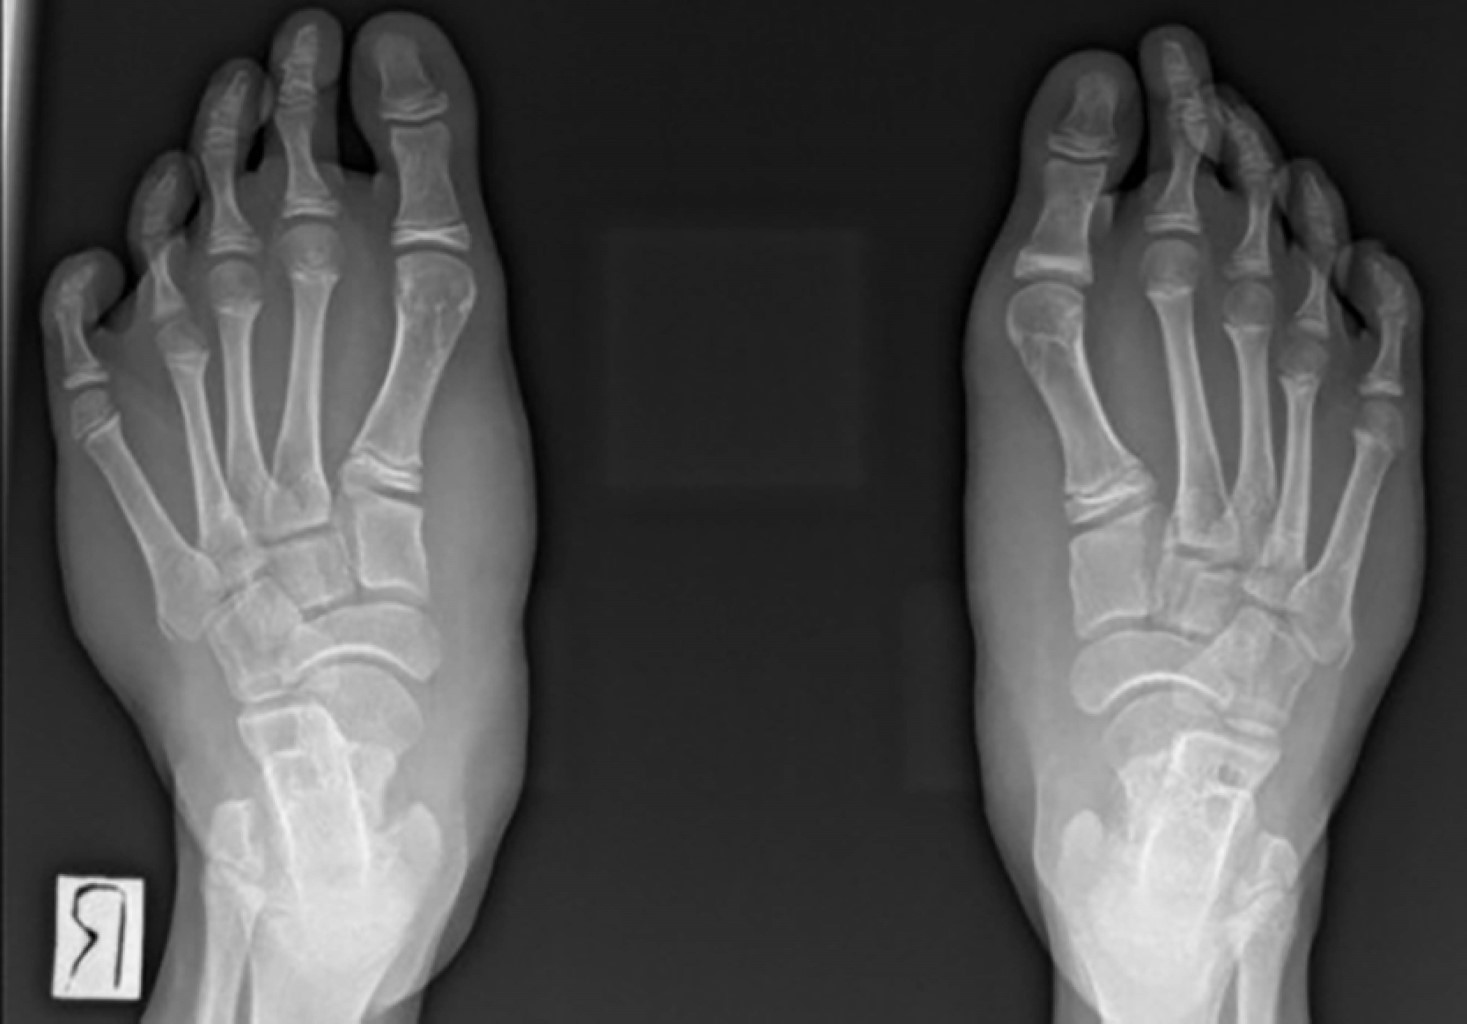

A la exploración física se evidenció aumento de volumen bilateral en ambos pies, de consistencia blanda, sin signos de inflamación; sin embargo, la amplitud del arco plantar anterior sobrepasaba la normalidad (Figuras 1 y 2).

Las radiografías simples de ambos pies mostraron aumento en los espacios intermetatarsianos y del ángulo intermetatarsiano, así como elongación de ambos calcáneos en comparación con los valores esperados para la edad del paciente (Figuras 5, 6 y 7).